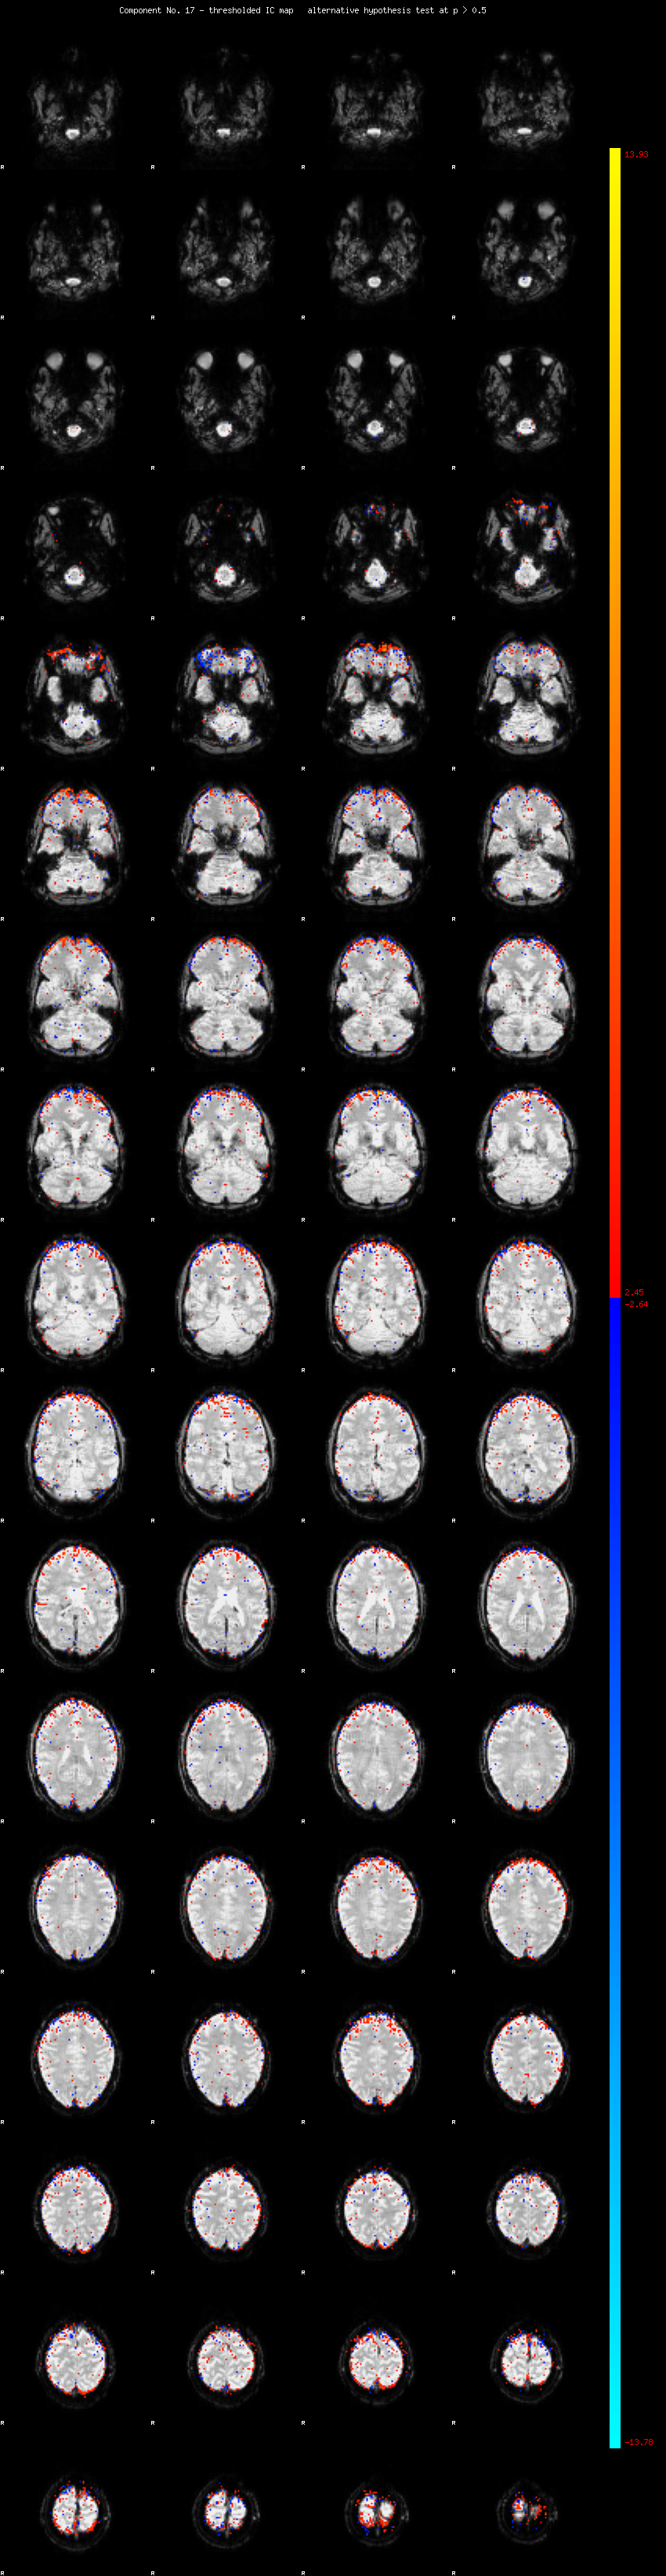

MELODIC Component 17

1.55 % of explained variance;     1.03 % of total variance